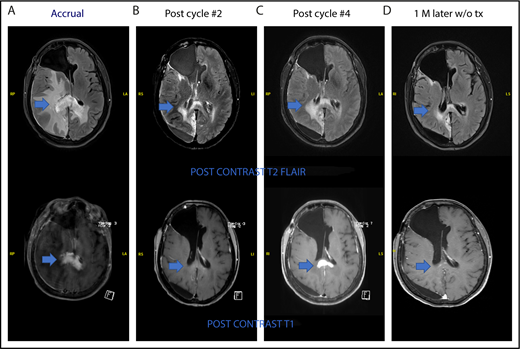

The ORR for all 25 eligible patients was 48% (12 of 25; 95% CI, 27.8%, 68.7%) with 6 CR, 2 CRu, and 4 PR (Figure 1). The ORR for the MTD dose level was 50% (8 of 16; 95% CI, 24.7%, 75.4%) with 5 CR, 1 CRu, and 2 PR. The ORR for the 23 PCNSL patients was 48% (11 of 23; 95% CI, 26.8%, 69.4%) with 6 CR, 2 CRu, and 3 PR. The 12 responders completed a median of 6.5 cycles (range, 2-42 cycles). Median DOR was 4.7 months (95% CI, 4.5-NE; range, 1.1-28.8 months). Median PFS was 5.3, 9, and 5.3 months for the whole study (Figure 1B), responders (Figure 1C) and PCNSL patients, respectively. The outcome events and total number of treatment cycles for each patient are summarized in a swimmer’s plot (Figure 2). Brain MRI of a PCNSL patient who achieved CR is shown in Figure 3. Two patients with PVRL were treated at the MTD dose level. One patient had disease progression after cycle 18. The other patient had PR after cycle 2 and remains on treatment after cycle 7.

One patient had stable disease after 2 cycles and developed radiologic progression on brain MRI after 4 cycles without any significant clinical deterioration. She was taken off the study as per protocol. Brain MRI 1 month later without steroid or any other treatment showed improvement (Figure 4). This appears to be a case of pseudoprogression. She went on to have treatment with single-agent ibrutinib followed by ASCT and is currently in complete remission.

Pseudoprogression in a PCNSL patient treated with pomalidomide. (A-B) The patient had stable disease after cycle 2 and (C) showed radiologic findings suggestive of progression of disease on restaging MRI of brain after cycle 4 without clinical deterioration. She was taken off study as per protocol. (D) Repeat MRI of brain 1 month later without any steroid or any other treatment showed radiologic improvement. This case is the patient 11 on Figure 2.